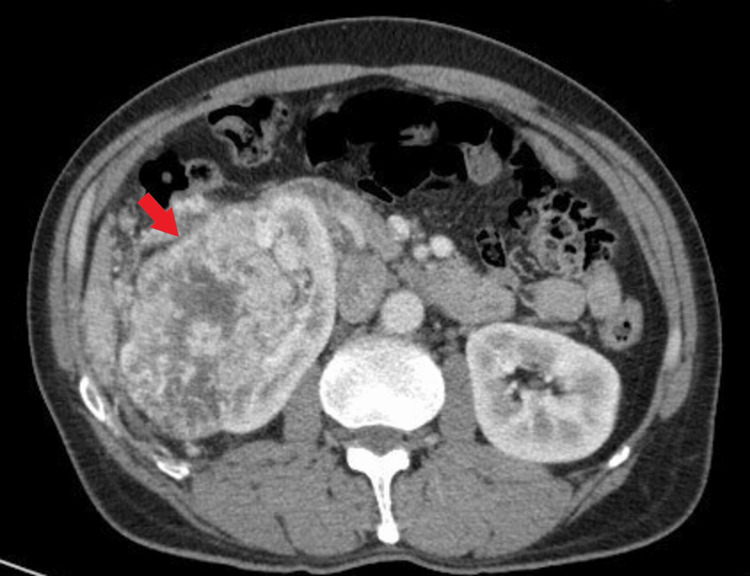

A 55-year-old heavy smoker male with no relevant medical history presented in September 2019 with flank pain and significant weight loss. Subsequent computed tomography (CT) scan revealed a right renal mass measuring 12.4×9 cm with no other pathologic findings (Figure 1).